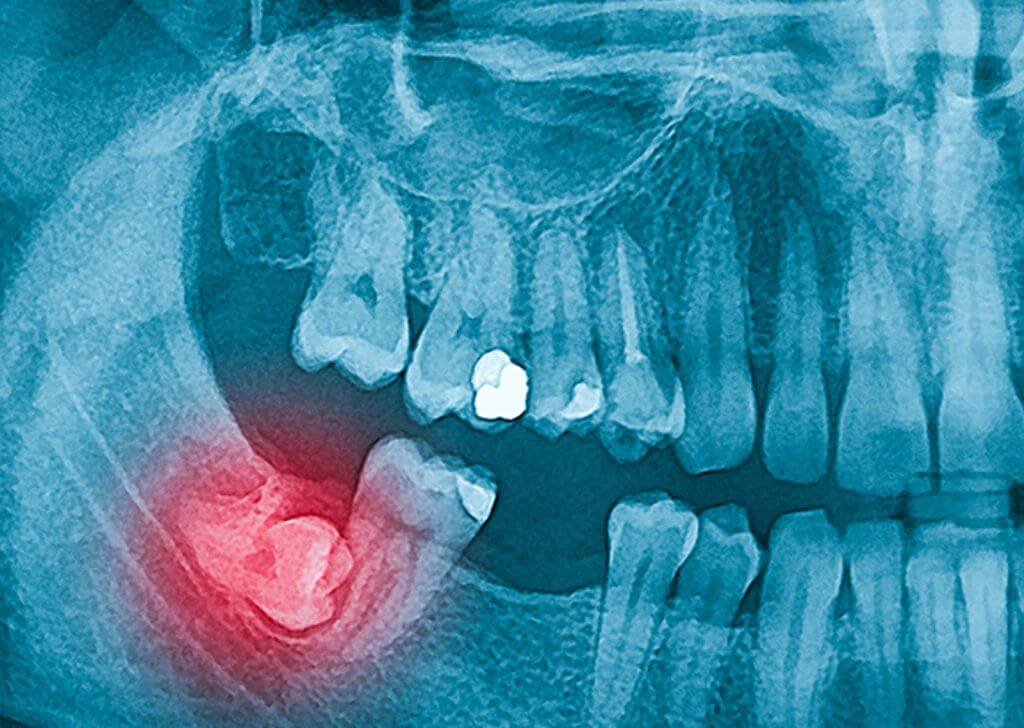

- Sista dan kerosakan tulang rahang – Dalam kes yang jarang berlaku, gigi bongsu terimpak boleh membentuk kantung cecair (sista) yang menyebabkan kerosakan tulang atau akar gigi bersebelahan.

Jika anda mula rasa sakit di bahagian belakang rahang atau gusi bengkak, langkah pertama ialah mendapatkan pemeriksaan doktor gigi. Imbasan X-ray biasanya diperlukan untuk menentukan arah tumbuh gigi bongsu dan sama ada ia perlu dicabut. Jangan abaikan gejala awal kerana gigi bongsu yang tumbuh senget boleh menyebabkan komplikasi lain seperti jangkitan atau gigi bersebelahan menjadi rosak.